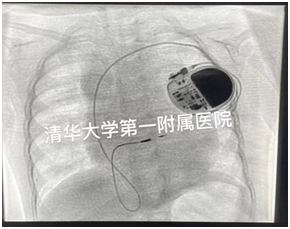

左束支起搏X光影像

2位小朋友在我院顺利接受了左束支起搏治疗,起搏参数满意,心电图显示QRS时限接近自身正常时间。7.1kg小希是目前我国最小体重婴儿的左束支起搏案例。